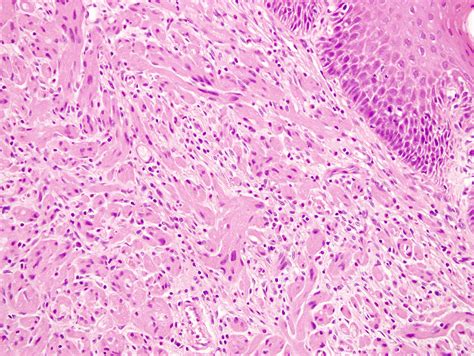

Histopathological Features

The histopathological features of granular cell tumours are distinctive and play a crucial role in their diagnosis. Key features include:

• Large, polygonal cells with abundant granular cytoplasm

• Small, centrally located nuclei

• Abundant lysosomes within the cytoplasm

• Positive staining for S-100 protein, a marker for neural and melanocytic differentiation

These features help differentiate GCTs from other types of tumours, such as rhabdomyomas and alveolar soft part sarcomas, which may have a similar appearance but different clinical behaviours.